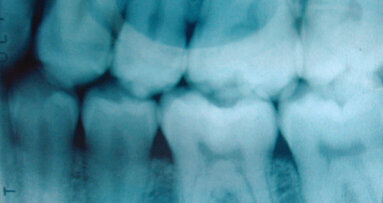

NEW YORK, USA/LEIPZIG, Germany: Researchers at the University of Illinois in the US could have discovered the key to re-growing tooth enamel. In a comparative study on animals, they found that repeated simple amino acids, or Prolines, are responsible for making teeth stronger and more resistant. Their findings could help in replacing lost parts of teeth in patients suffering from dental decay.

Proline is a major component of the protein collagen, the connective tissue structure that binds and supports all other tissues. It can be also found in protein bubbles that help to form enamel.

In the study, the researchers compared the number of Proline repeats in amphibian and mammal models, such as mice, cows and frogs, and discovered that when the repeats are short, teeth lack the enamel prisms that are responsible for the strength of human enamel. In contrast, when the Proline repeats are long, they contract groups of molecules that help enamel crystals grow.